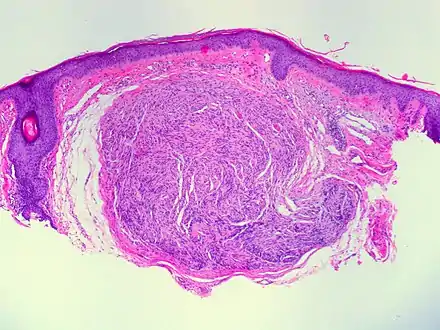

| Micrograph of a palisaded encapsulated neuroma | |

Palisaded encapsulated neuroma (PEN) is a rare, benign cutaneous condition characterized by small, firm, non-pigmented nodules or papules.[1][2] They typically occur as a solitary (single) lesion near the mucocutaneous junction of the skin of the face, although they can occur elsewhere on the body.[3]

As mentioned previously, PEN is a benign, firm, flesh-coloured lesion that typically occurs in dermis of the skin of the face. The lesions are typically between 2–6mm and are slow-growing.[3][4]

PEN is diagnosed by clinical recognition of the lesion and on subsequent histologic examination. Typically, the lesions are suspected to be schwannomas or neurofibromas clinically with PEN being an incidental finding on histology.[3]

PEN is typically diagnosed in patients between the ages of 40 and 60 years and occurs more frequently in females than males. The diagnosis of PEN may be difficult, even with confirmatory histology, due to its histological similarities with schwannomas and neurofibromas. It is imperative that the correct diagnosis is made the misdiagnosis of a neurofibroma may lead to unnecessary further investigation into associated systemic syndromes such as neurofibromatosis type 1 or multiple endocrine neoplasia syndrome.[3][4]